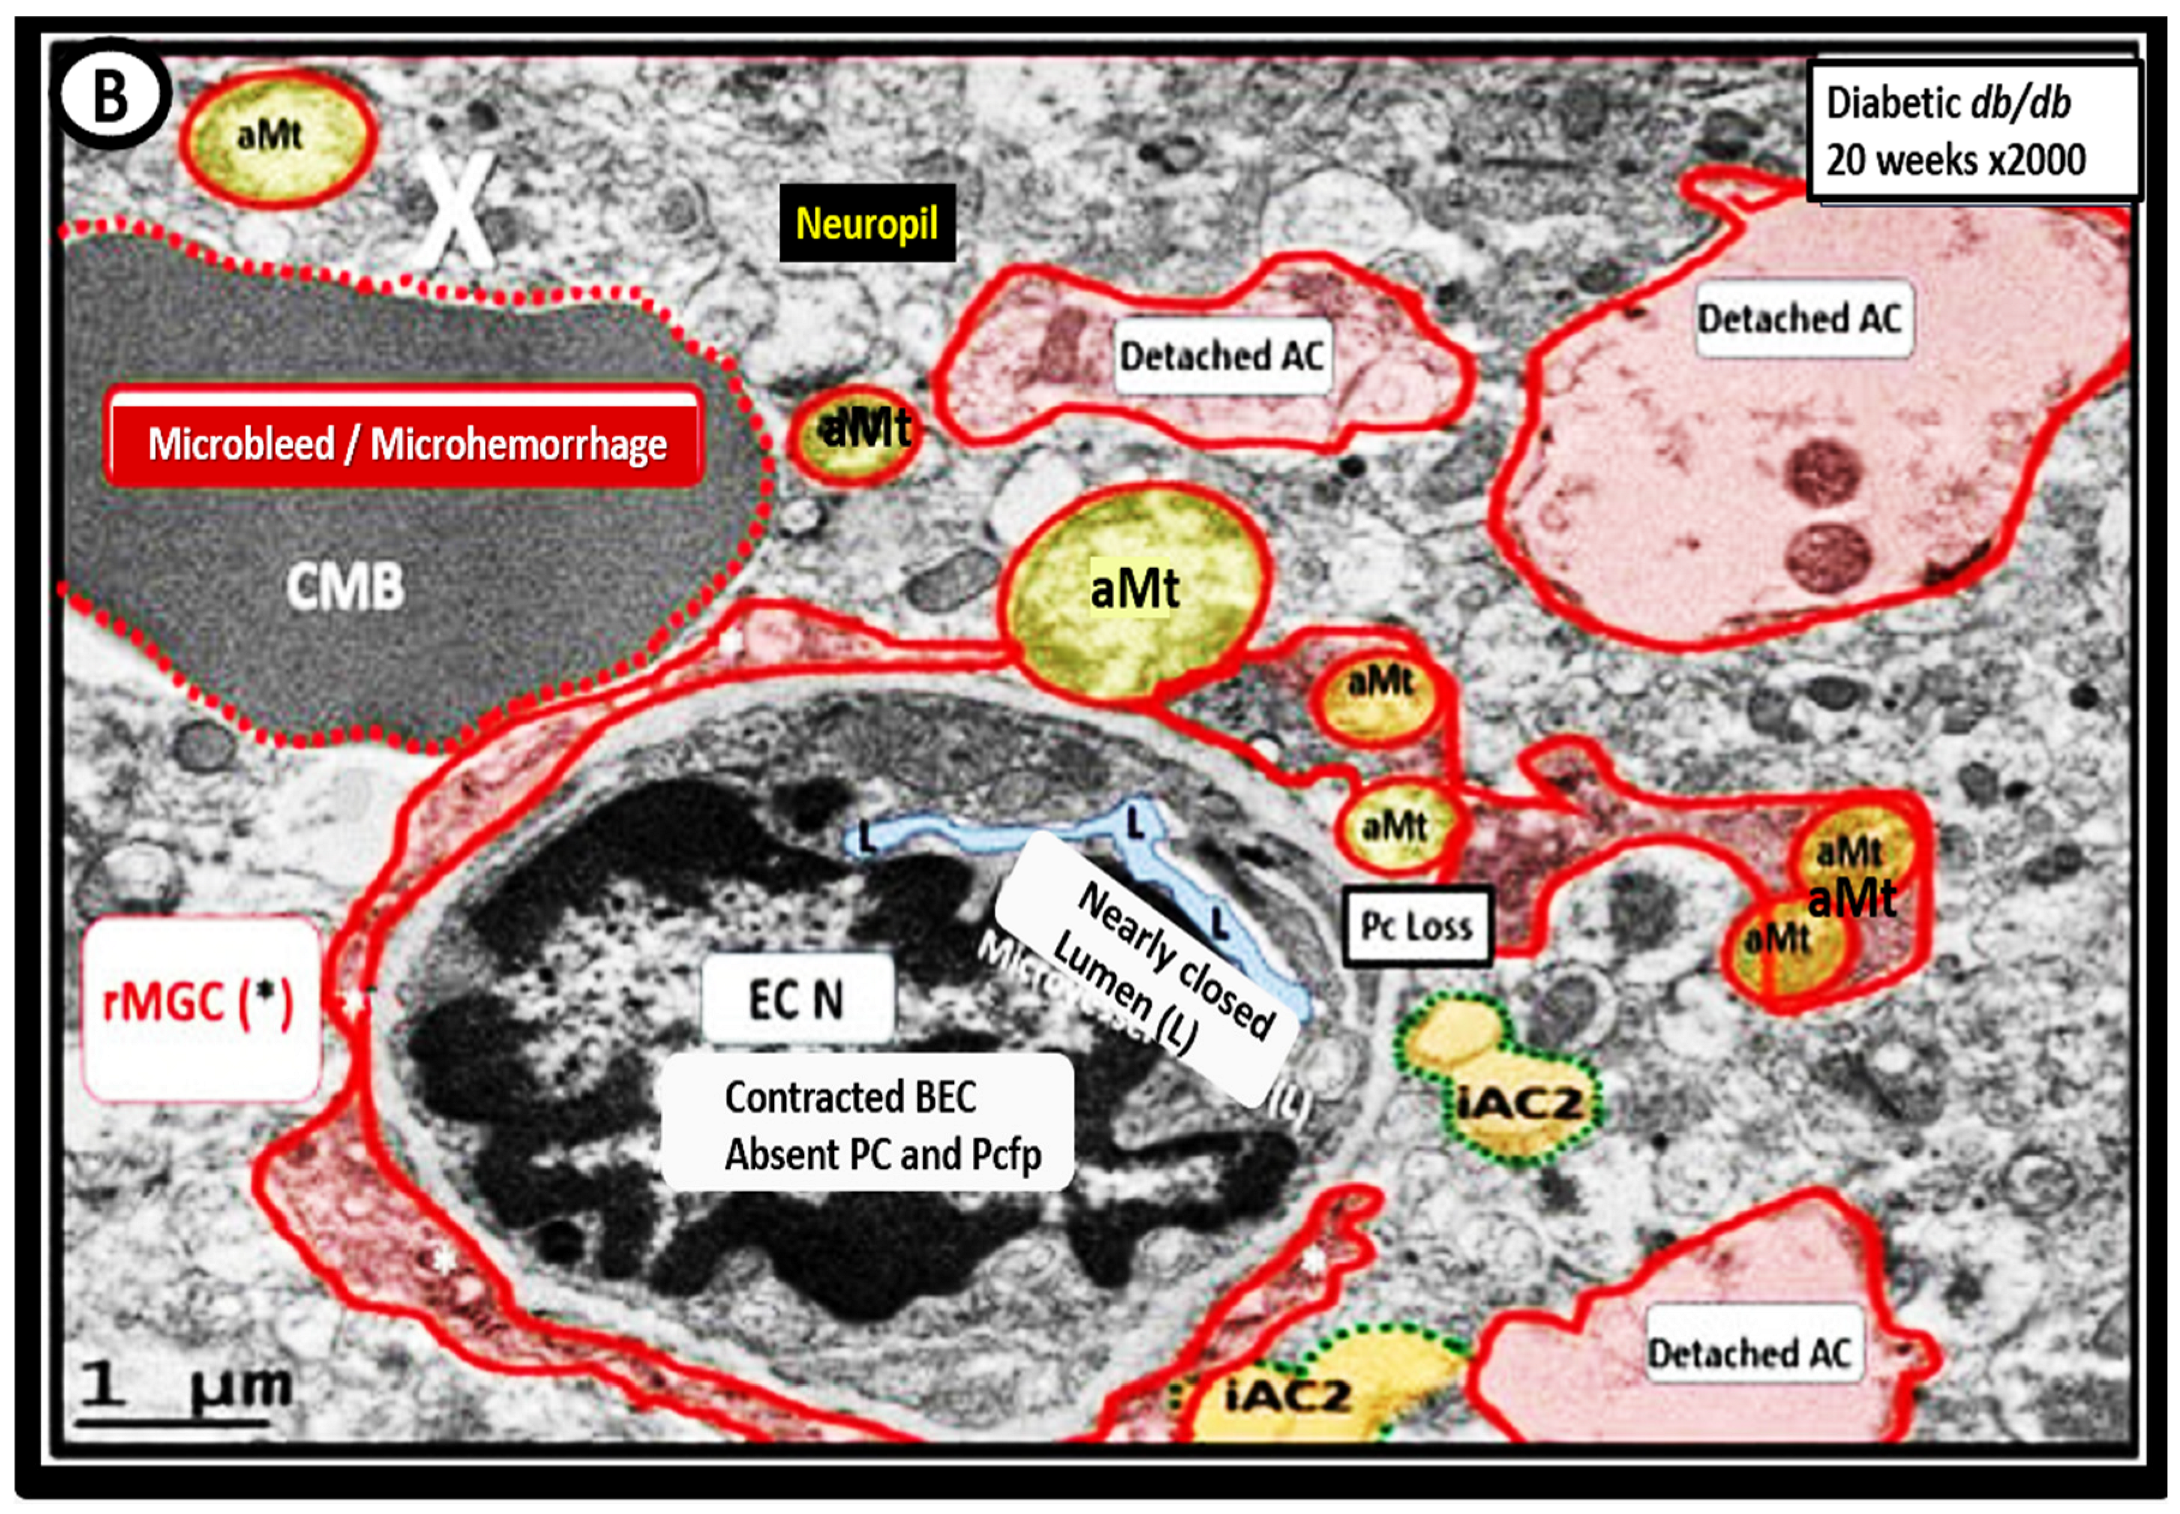

3. Transmission Electron Microscopy (TEM) Imaging of BECact/dys), BBBdd with CMBs

- Hayden, M.R. Type 2 Diabetes Mellitus Increases the Risk of Late-Onset Alzheimer’s Disease: Ultrastructural Remodeling of the Neurovascular Unit and Diabetic Gliopathy. Brain Sci. 2019, 9, 262. [Google Scholar] [CrossRef]

- Hayden, M.R.; Grant, D.G.; Aroor, A.R.; DeMarco, V.G. Ultrastructural Remodeling of the Neurovascular Unit in the Female Diabetic db/db Model—Part I: Astrocyte. Neuroglia 2018, 1, 220–244. [Google Scholar] [CrossRef]

- Hayden, M.R.; Grant, D.G.; Aroor, A.R.; DeMarco, V.G. Empagliflozin Ameliorates Type 2 Diabetes-Induced Ultrastructural Remodeling of the Neurovascular Unit and Neuroglia in the Female db/db Mouse. Brain Sci. 2019, 9, 57. [Google Scholar] [CrossRef] [PubMed]